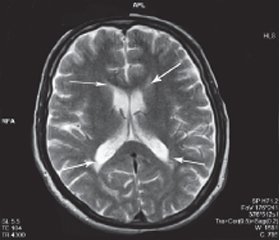

Хроническая ишемия головного мозга и лейкоареоз: симптомы и лечение